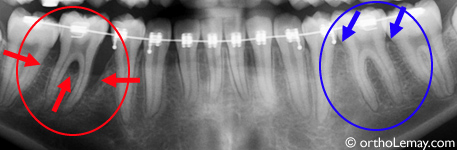

La première molaire inférieure gauche a un niveau osseux normal (flèches bleues) tandis que celle de droite (rouge) a une perte importante (presque 50%) du niveau de l’os ce qui met en péril la survie de la dent. Un suivi en parodontie est essentiel pour tenter de corriger cette situation.

Les problèmes de perte et de destruction osseuse autour des dents sont souvent généralisés ou affectent, la plupart du temps, plusieurs dents. Dans des cas plus rares, la perte osseuse peut n’affecter qu’une seule région de la bouche, comme le démontre l’exemple suivant.